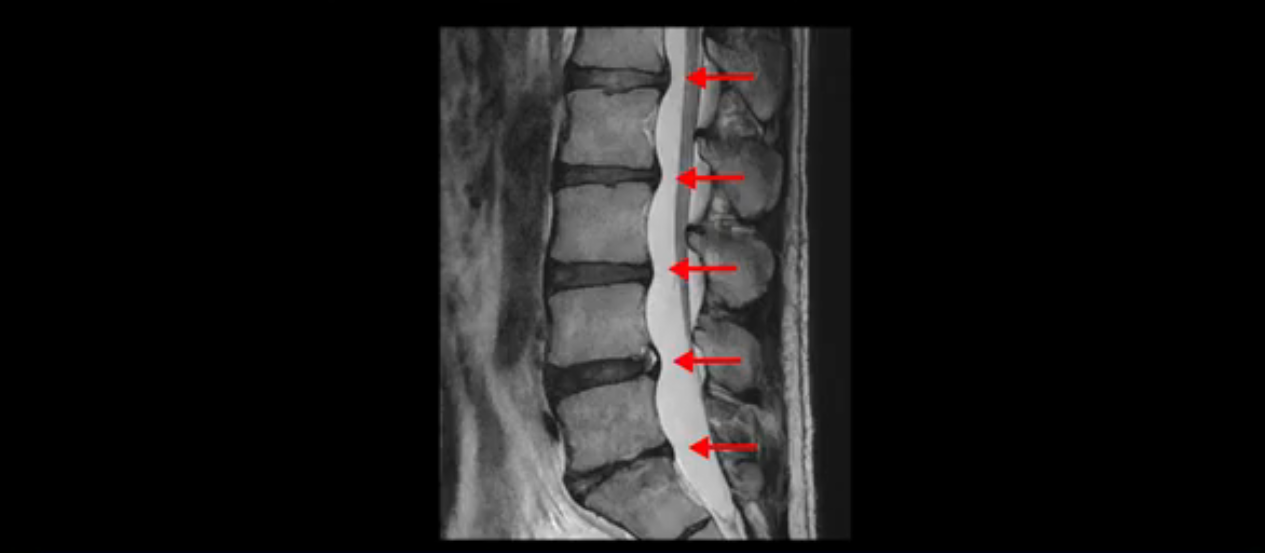

그런데 이분의 증상과 MRI가 전혀 일치하지 않는데, 왜 그런지 지금부터 자세히 설명드립니다. 이분 증상은 앉으면 엉치와 허리가 심하게 아파 10분 이상 앉는 게 어렵고 양쪽 발가락이 앉아있을 때나 누워있을 때 다 저립니다. 걸을 때도 아파서 10분 걷기도 어렵습니다. MRI를 마디마디 살펴보면 1번 2번은 오른쪽으로 살짝 밀려나온 디스크가 있지만 전혀 심하지 않고, 뒤에 또 설명하겠지만 최근에 밀려나온 급성 디스크가 아니고 오래된 디스크로 판단됩니다.

2번 3번도 비교적 디스크 상태는 좋고 신경 구멍 넓이도 아주 넓습니다.

3번 4번도 마찬가지로 디스크상태 좋아 보이고 신경 눌림 전혀 없어 보입니다.

4번 5번은 가운데로 섬유륜이 찢어져서 디스크가 살짝 밀려나와 있지만 역시나 최근에 찢어지고 밀려나온 걸로 판단되지 않고 오래 전에 찢어진 흔적으로 보입니다.

왜 최근에 찢어진 급성이 아니고 오래된 거라고 하는지 이 부분도 뒤에 한꺼번에 설명 드리겠습니다.

5번 1번 역시 가운데로 디스크 조금 밀려 나와있지만 신경 공간 넓이는 아주 넓어서 신경 눌림 있을 거라고 예상이 안됩니다.